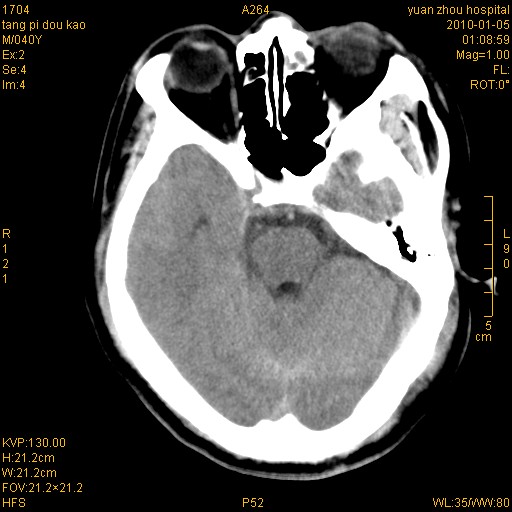

1)左侧颞枕部硬膜外血肿。2)右侧额部硬膜下血肿。3)双侧额叶及右侧基底节下部脑挫裂伤。4)蛛网膜下腔出血。5)脑水肿。6)左侧前组筛窦及左侧额窦炎症。

+左侧颧骨骨折。

左侧颧骨骨折